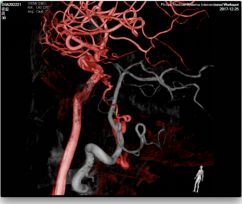

头颅MRA未见颅内异常血管,但头颅MRI-TOF像可见左侧天幕缘异常血管影(图2),CT薄层增强扫描见枕骨大孔区异常血管影(图3)。于2017年12月25日局麻下行全脑及全脊髓血管造影,脊髓血管造影未见异常,双侧椎动脉造影未见异常,最后行左侧颈内动脉造影示脑膜垂体干供血的天幕区硬脑膜动静脉瘘,瘘口位于岩骨中内1/3,直接经桥脑中脑侧静脉、扩张的延髓周围静脉向脊髓前静脉引流(图4)。造影诊断:左侧天幕区硬脑膜动静脉瘘。

图2. MRA未见异常,MRI-TOF示左侧天幕缘异常血管影(箭头所示)

图3. CTA见枕骨大孔区异常血管(箭头所示)

图4. DSA血管造影